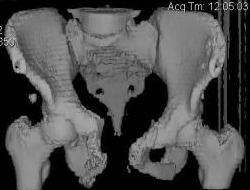

Уважаемые коллеги! Девушка 18л сросшиеся переломы лонных, седалищных костей с обеих сторон, перелом крестца справа,перелом костей голени справа (зио), 3 мес после травмы, АВФ снят с таза. Патологической подвижности нет. Стоит самостоятельно, ходит с костылями, поскольку 3 месяца практически не ходила. Беспокоит выступание лонной кости в области лобка, хотя объективно грубого косметического дефекта нет. На кт разворот лонной кости в сагиттальную плоскость. Вопрос: стоит ли добиватьсяполной репозиции или же достаточно произвести остеотомию верхушки выступающего отломка?

Предварительный диагноз- посттравматическая вертикальная нестабильная деформация таза II степени, неправильно срастающийся перелом боковой

массы крестца справа, правой лонной и седалищной костей, застарелый разрыв лонного сочленения.